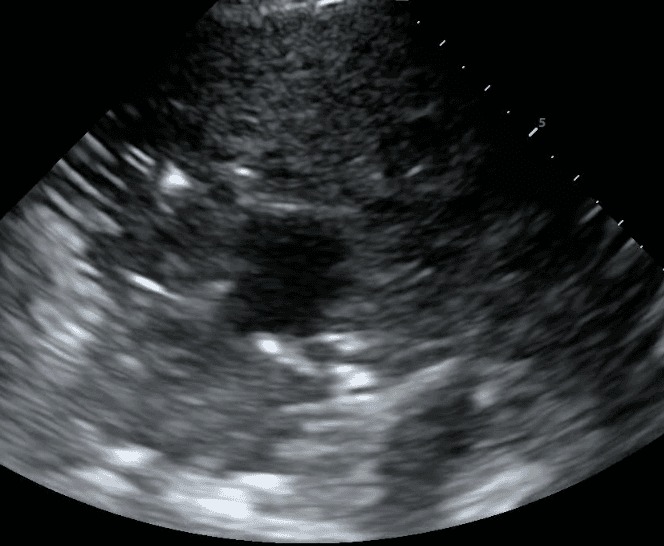

Pleural space pathologies comprise any disease affecting the thin, fluid-fill area between the visceral and parietal pleura. These conditions typically involve the excess accumulation of air (pneumothorax), fluid (ie. pleural effusion), blood (hemothorax) or pus (empyema), expanding the space between the pleural layers. This impedes normal lung function and can lead to significant respiratory distress if left untreated.

In contrast, pleural effusion, hemothorax and empyema may all present with thickening of the pleural line, but can usually be differentiated based on the presence of anechoic fluid, bright echogenic material or septations (read more here). With lung ultrasound, physicians can diagnose and initiate treatment such as chest tube insertion or antibiotics without leaving the bedside.